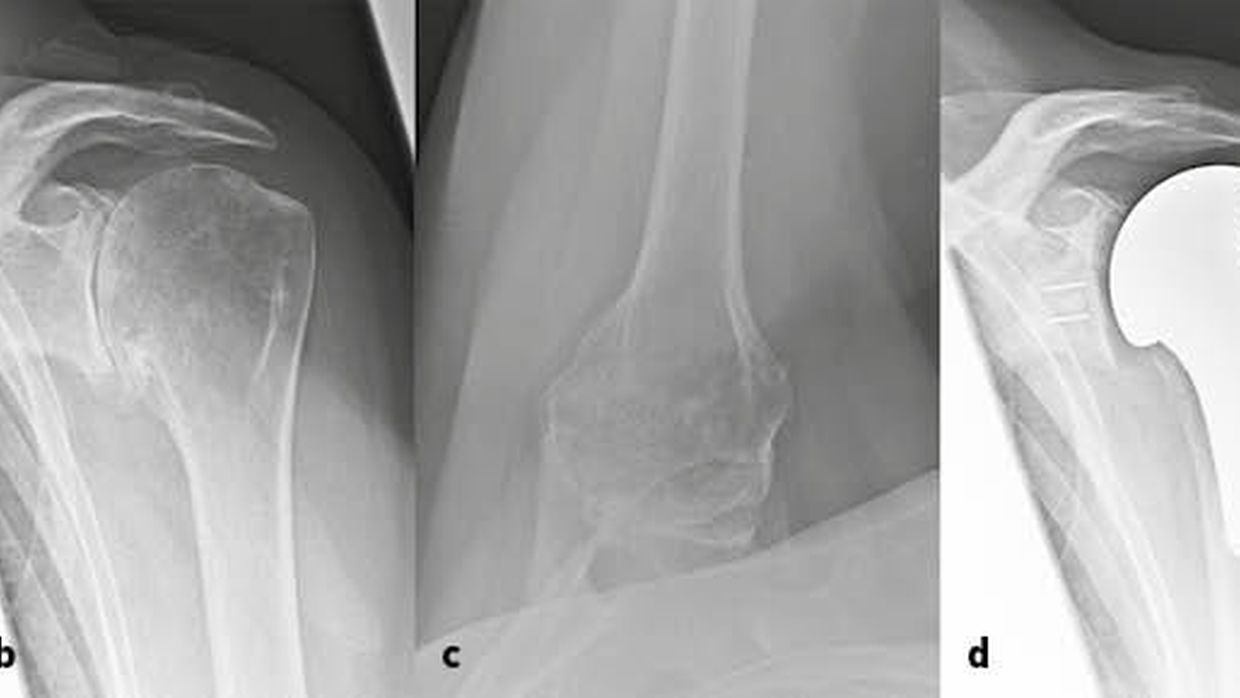

From www.orthobullets.com

Shoulder Periprosthetic Fracture Shoulder & Elbow Orthobullets History Of Shoulder Arthroplasty The idea of reverse total shoulder arthroplasty (rtsa) was first introduced in 1974 by charles neer and has considerably progressed ever. 77 the procedure was performed for tuberculosis of. The first shoulder arthroplasty was performed in 1893. The first shoulder arthroplasty was performed in 1893 by the french surgeon jules pean for a case of destruction of the shoulder. The. History Of Shoulder Arthroplasty.